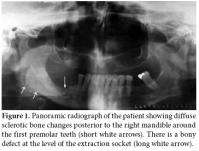

In September 2008, a 58-year-old female diagnosed with AS in 1973 was referred to Ege University Hospital, Department of Physical Medicine and Rehabilitation complaining of pain and discomfort in the right mandible. These symptoms had started in May 2008 following a tooth extraction. The extraction socket did not heal, even after eight weeks, despite antibiotherapy. Besides the pain and discomfort, she experienced the presence of some particles in the tooth extraction socket of her right mandible which were probably autogenous bone. A panoramic radiograph was taken 10 weeks later in July 2008 which revealed irregularity and diffuse sclerotic bone changes in the trabecular bone structure of the right mandible as well as a bony defect at the level of the extraction socket (Figure 1). A sample obtained from the exposed area was sent for culture to the microbiology laboratory due to the suspicion of dental infection/abscess. Oral flora microorganisms grew in the culture.

Together with the past history of long-term alendronate treatment and occurrence after tooth extraction, relevant clinical symptoms and conventional radiographic findings led to the suspicion of ONJ in this patient. We immediately ordered dental computed tomography (CT) which revealed sclerosis and osteolytic changes in the right mandible. This confirmed the diagnosis of osteonecrosis (Figures 2, 3). The patient also consulted with dental surgeons, and since there was no pathologic fracture, extra-oral fistulae, or osteolysis extending to the inferior border of the mandible, the disease was accepted to be in the second stage. Surgery was not recommended, and conservative management was started. The patient was advised to discontinue the alendronate treatment, and the etanercept treatment was also stopped. A good oral hygiene regimen using antibacterial tooth rinse was recommended. Her complaints and symptoms alleviated gradually. A control panoramic radiography taken after one year of bisphosphonate withdrawal displayed healing of the exposed bone (Figure 4).